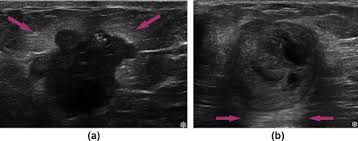

The rate of breast cancers discovered as dcis is thought to be increasing, but this is partially a testament to the effectiveness of mammographic breast cancer screening programs.ductal carcinoma in situ represents up to 30% of all new cases of breast cancer discovered by breast cancer screening. On ultrasound, a breast cancer tumor is often seen as hypoechoic, has irregular borders, and may appear spiculated. A specialist looks at the ultrasound pictures. Depending on your symptoms, your doctor makes a diagnosis based on a combination of tests and procedures. Below are images of dcis on breast ultrasound. If there are calcifications within the nodular dcis, one may be able to see these on ultrasound as white flecks. Is tender, aches or feels painful. X trustworthy source mayo clinic educational website from one of the world's leading hospitals go to source research suggests that men are more likely to ignore breast lumps than women, but early. During a breast exam, your doctor looks for visual changes and uses their fingers to feel. What does breast cancer look like on a mammogram? The symptoms of ibc include a breast that: (1) gary ulaner, md, phd, facnm. Notice that there is some fibroglandular tissue on the right, while on the left there is only subcutaneous fat.

However, a dark spot on your ultrasound doesn't mean that you. Characteristics of malignant breast cancer on ultrasound are speculation, deeper (taller) than wide, microlobulations, thick hyperechoic halo, angular margins, markedly hypoechoic nodule, posterior acoustic shadowing, branching pattern, punctate calcifications, duct extension and heterogeneous echotexture. Signs of inflammatory breast cancer. Mammography is the least sensitive imaging. Breast ultrasound breast ultrasound uses sound waves to make a computer picture of the inside of the breast.

A A Simple Breast Cyst 75 B Breast Ultrasound Showing A Cancer Download Scientific Diagram from www.researchgate.net Instead, breast skin can become thick, red, and look pitted, like an orange peel. Signs of inflammatory breast cancer. Ultrasound images are black and white, showing a small portion of the breast at a time. Below are images of dcis on breast ultrasound. Ibc is a rapidly progressive, aggressive form of breast cancer associated with a low overall survival rate. Looks larger, thicker or heavier. X trustworthy source mayo clinic educational website from one of the world's leading hospitals go to source research suggests that men are more likely to ignore breast lumps than women, but early. Finding breast lumps and seeing change in the size and shape.